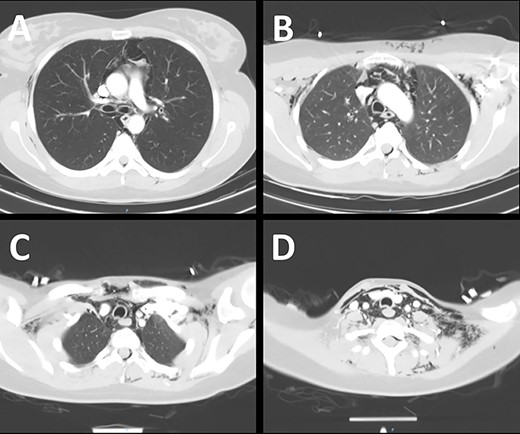

An enhanced CT scan of the neck and chest demonstrating extensive surgical emphysema and pneumomediastinum.

An enhanced computed tomography (CT) scan of the neck and chest is shown in Fig. 2. This demonstrated extensive pneumomediastinum (A), as well as subcutaneous emphysema extending from the chest wall (B) into the soft tissues of the neck (C and D). Air was noted to have leaked into the spinal canal. Imaging did not reveal a tracheal tear or airway injury.